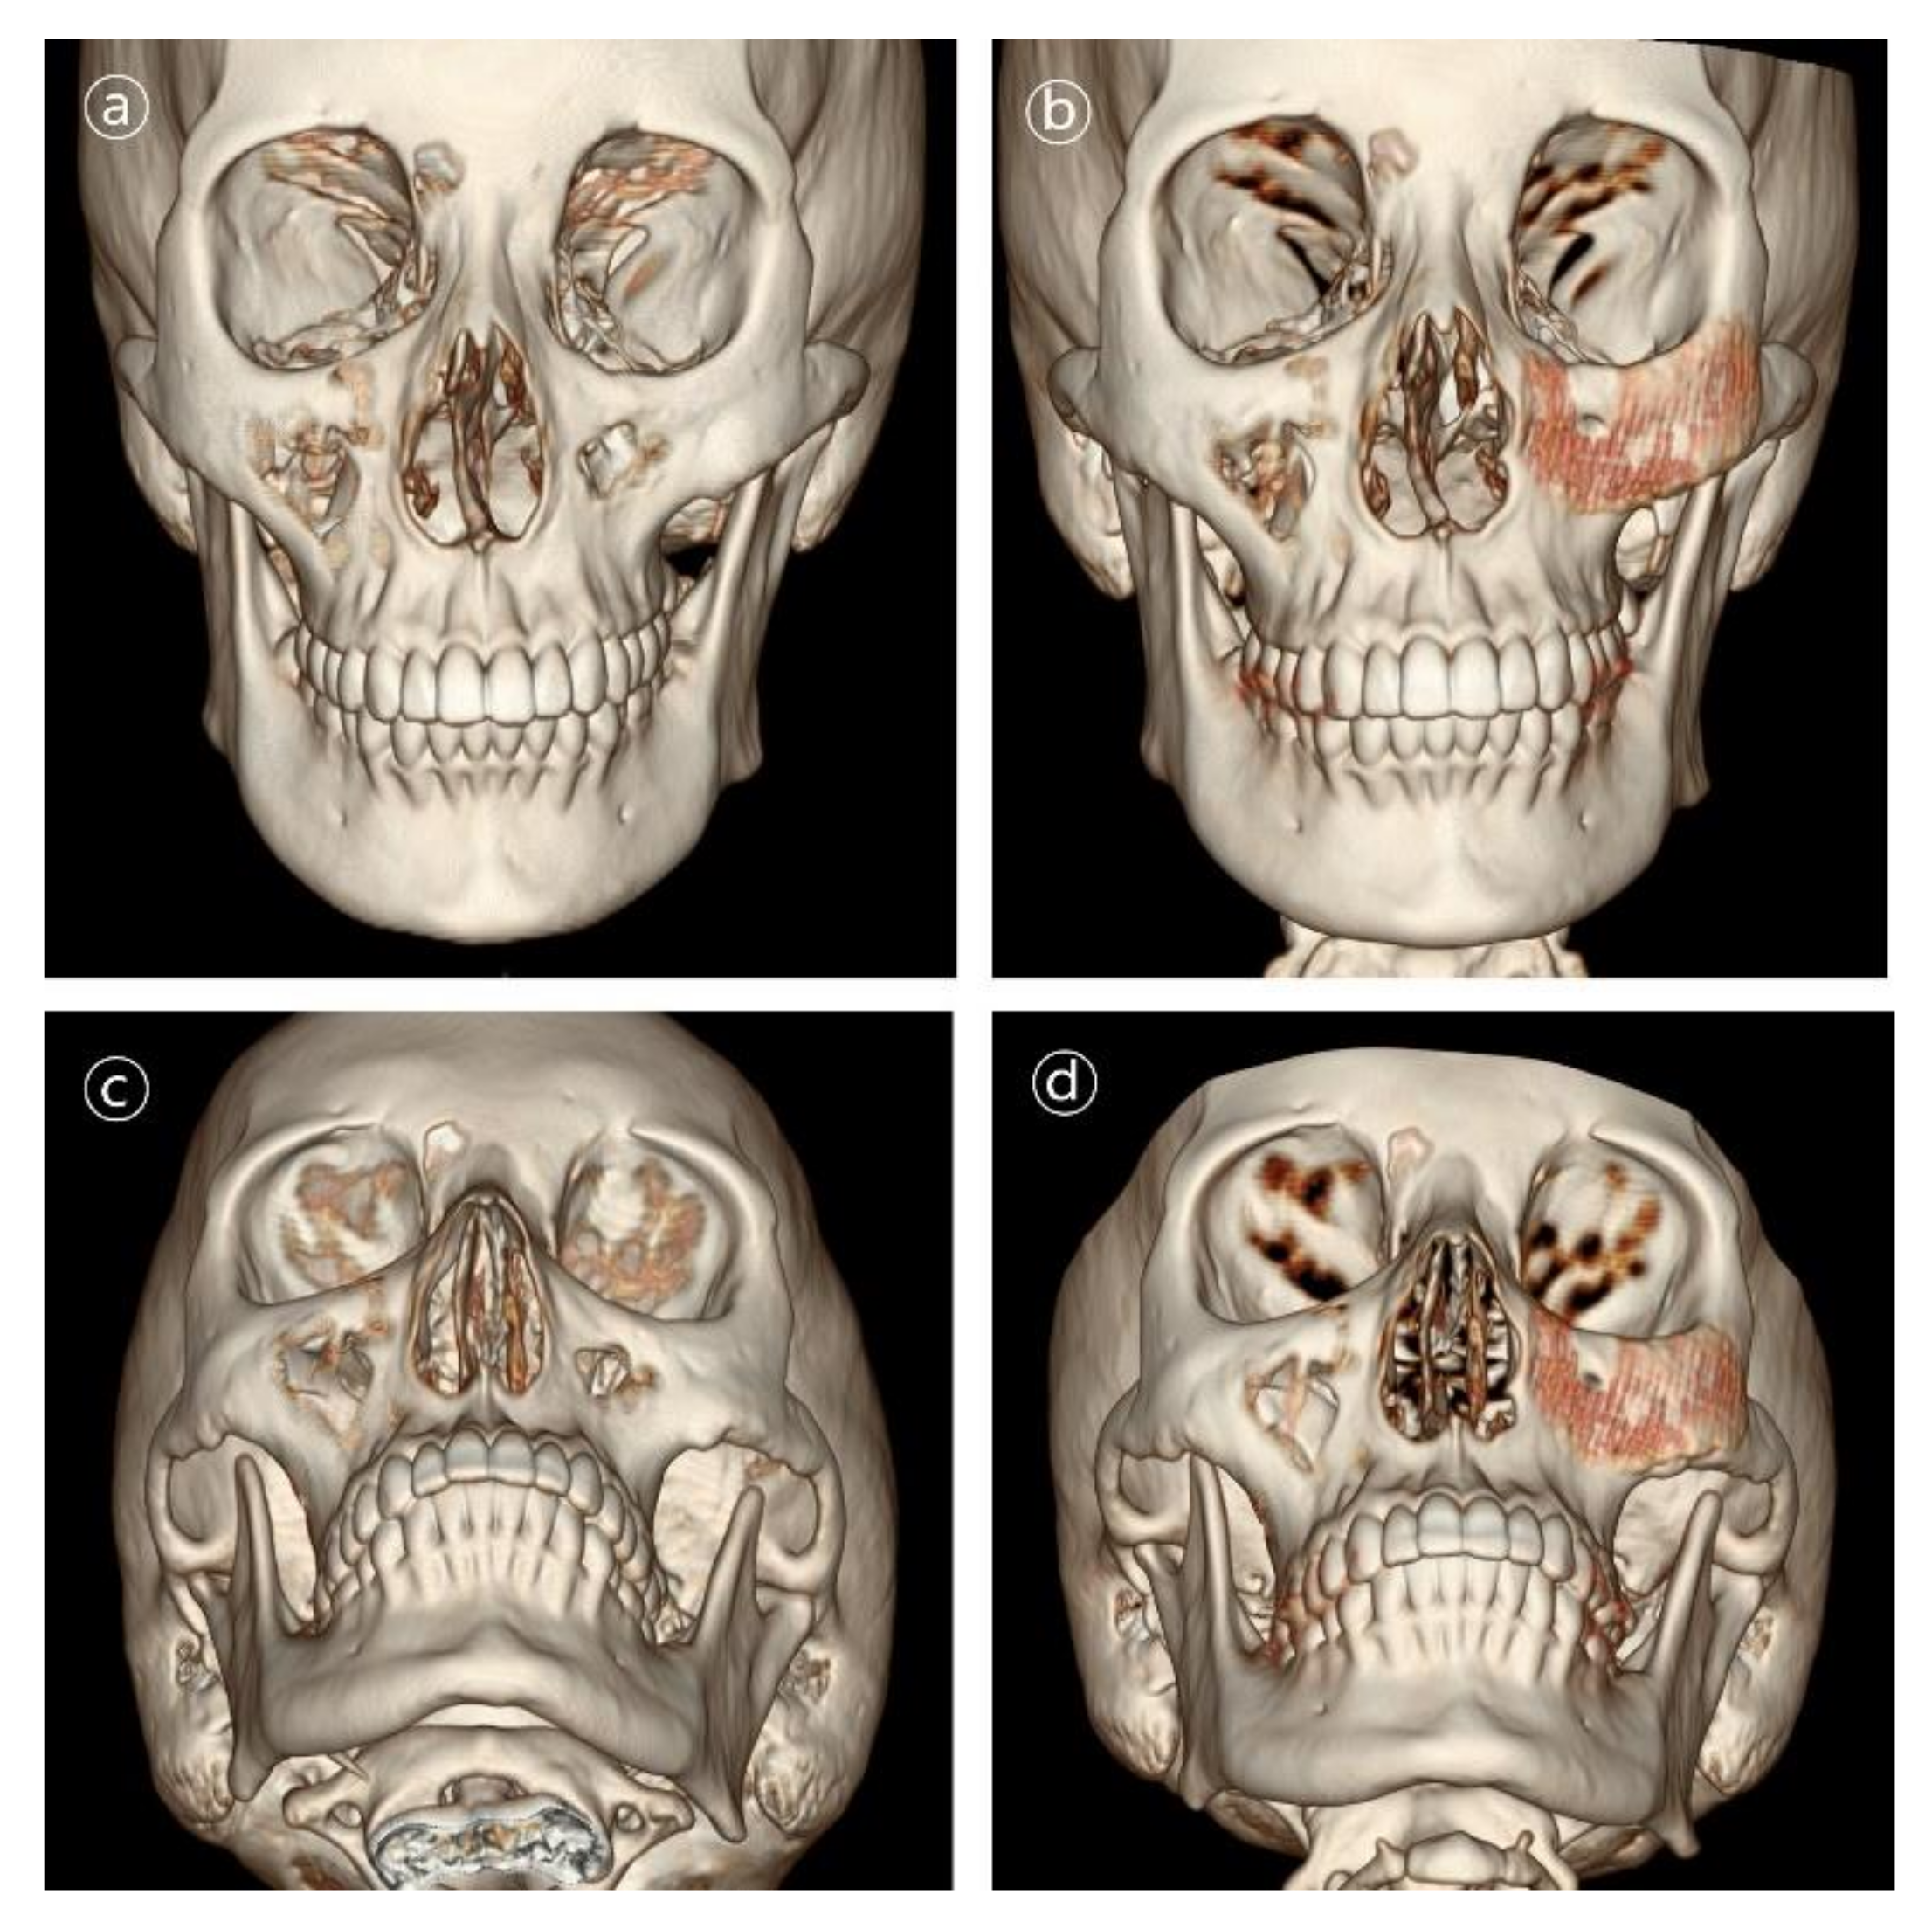

Figure 8. 3D CT images in patient #5. Contour and symmetry of left zygomatico-maxillary region was improved. (a,b) Pre- and postoperative 6-month frontal view CT images. (c,d) Pre- and postoperative 6-month basal view CT images.

Patient #5 was 21-year-old male who underwent immediate reconstruction following the en bloc resection of maxillary fibrous dysplasia, defined as a type V defect. The patient underwent reconstruction with the 3D-printed PCL/β-TCP scaffold through a conventional gingivobuccal and transconjunctival incisions. The 3D-printed implant was fixated with wire steel. There was no complication in the long-term follow-up (Figure 7 and Figure 8).